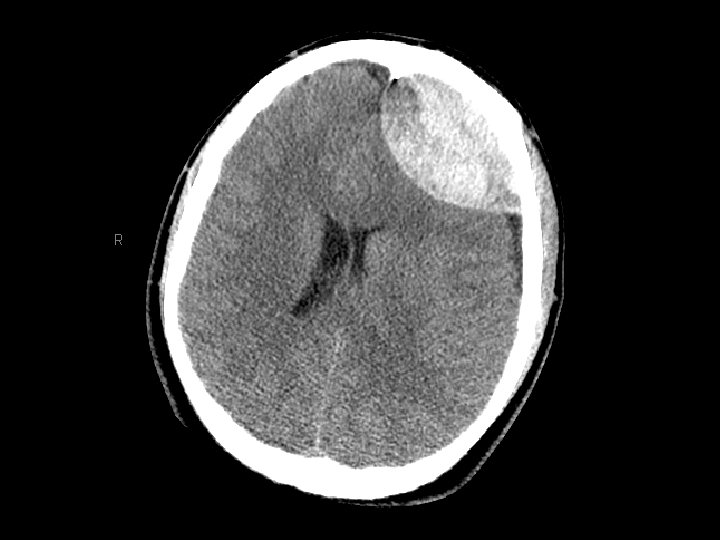

Tụ máu dưới màng cứng • Chảy máu giữa màng cứng và não – Thường gặp hơn tụ máu ngoài màng cứng – 30% bệnh nhân CTSN có tụ máu dưới màng cứng • CT: khoảng tụ máu hình liềm • Có thể gặp cấp tính, bán cấp hoặc mãn tính – Bán cấp hoặc mãn tính diễn biến nhiều ngày/tuần sau chấn thương

Tụ máu dưới màng cứng • Tăng nguy cơ ở người già (cơ chế chấn thương không nghiêm trọng) – Não teo nhỏ đi theo lứa tuổi gây giãn các tĩnh mạch cầu nối ở khoảng dưới màng cứng • Có thể tăng dần kích thước (chậm hơn máu tụ ngoài màng cứng) • Phẫu thuật dẫn lưu nếu tổn thương gây choán chỗ và đè đẩy